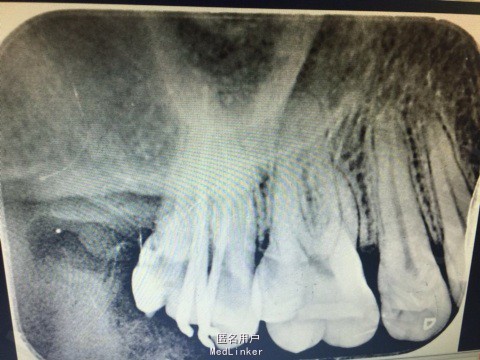

主诉:患者右上后牙冷热刺激痛数日。 病史:数日来,患者右上后牙冷热刺激疼痛不适,偶有自发痛影响进食,来院就诊。

查体:17远中颈部龋坏,探(+),冷热诊疼痛明显且持续较长时间。叩(-),X线示17远中颈部龋坏深达牙髓腔。

诊断:17深龋伴牙髓炎 治疗: 局麻下17去腐,开髓揭髓顶降牙合,冲洗髓腔,拔髓疏通根管,测量根管镍钛器械进行根管预备,低浓度次氯酸钠进行根管的冲洗化学预备,拭干根管,进行根管试尖,X线示恰充,进行热牙胶垂直加压连续波充填法进行根管充填。暂封进行嵌体修复。